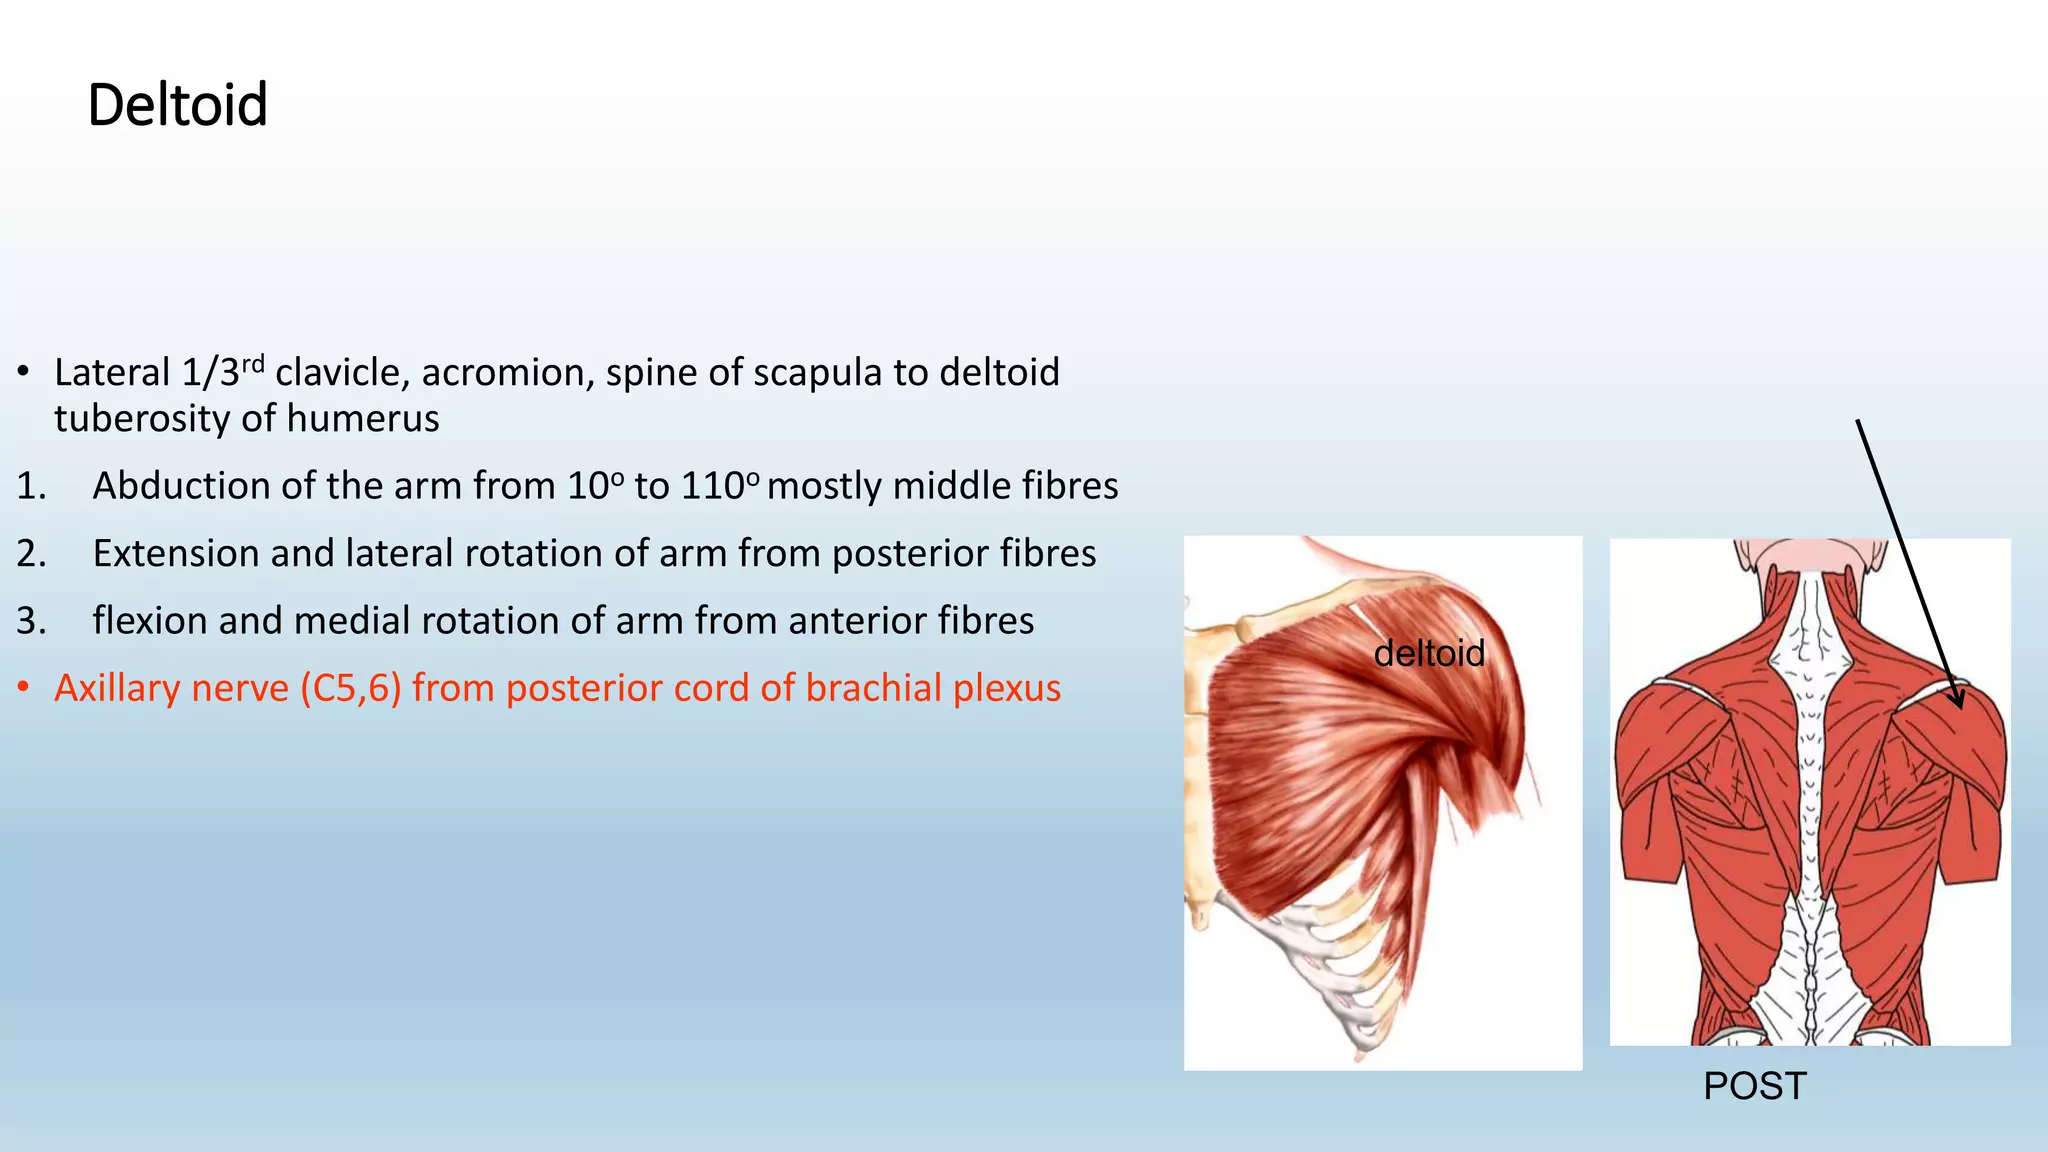

The document summarizes an anatomy revision session on the upper limb. It discusses various muscles of the upper limb including their origins, insertions, innervations and functions. Key muscles covered include the pectoralis major and minor, serratus anterior, deltoid, biceps brachii, brachialis, coracobrachialis, and triceps. It also discusses the rotator cuff muscles and muscles of the forearm including flexor carpi ulnaris and radialis. The session aims to help students identify upper limb muscles and understand their relations to nerves.